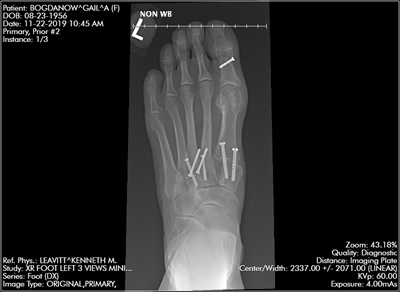

Pleased with Hammer Toe/Bunion Reconstructive Surgeries

By Gail Bogdanow

"We bought a knee walker that proved indispensable. We also borrowed a tub transfer bench from our town's senior center for showering as well as a dry cast protector. Every home is different but there are some preparatory basics. There were seven weeks in a cast followed by learning to walk again and several weeks using the Dynasplint devices. I was so pleased with the outcome that I had the second, less deformed foot, reconstructed as well. I am just as pleased with the results and my marriage is still strong."